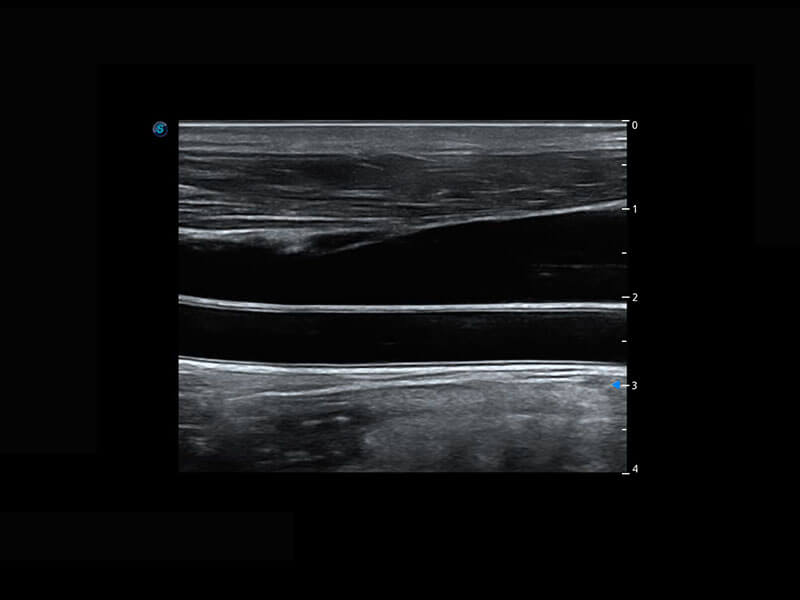

P60为盆底超声检查提供应用方案,多种腔内及腹部容积探头提供从二维、三维到四维的优异图像品质,实时快速三维容积数据获取,专业的测量工具包等人性化设计,为超声医生诊断提供有力保障。

Lev.Hiat A-r: 16.33 cm2

Lev.Hiat H-r: 53.70 mm

Lev.Hiat W-r: 43.96 mm

Lt-LUG-r: 24.16 mm

Rt-LUG-r: 19.94 mm

能够简化盆底检查的操作流程,可在二维模式及三维成像模式下实现一键自动提取出标准切面、自动识别当前切面、自动测量,提升盆底检查的高效性,同时也能让青年医生快捷的获得准确的检查结果。